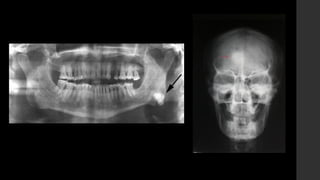

Osteoma.

• RX 

Masa densa, esclerótica con aspecto de marfil, con

márgenes definidos, unida al hueso.

• TC 

Es eficaz para demostrar la ausencia de invasión cortical.

• IRM

Imágenes con señal baja en T1 y T2 sin realce.

Adam Greenspan et al. Tumores osteoblásticos (formadores de hueso). Tumores de huesos y articulaciones. Capítulo 2. PP. 25 – 26.